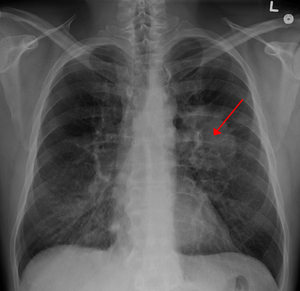

在肺癌患者中,最主要的 肺癌症状 就是咳嗽,刊登在《美国胸科杂志》上的一项研究发现,约60%的肺癌患者在正式确诊时有慢性咳嗽症状。但是普通感冒、咽喉炎也会咳嗽,这就导致了很多肺癌患者在早期咳嗽时并没有引起重视,没有及时就医进行检查,最终错过 ...

在肺癌病人中,咳嗽、咯血咳嗽是最常见的 肺癌早期症状 。咯血则最有诊断意义,多为痰中带血丝。凡呼吸道症状超过两周经治不愈,尤其是痰带血、干咳或老年慢性支气管炎病人,近期咳嗽声音或性质改变,要高度警惕肺癌的可能。由于咯血的量少或间歇出现, ...

肺癌,它高居全球癌症首位,很多病人认为肺癌一定会有咳嗽、咳痰和痰中带血的表现,其实这样的观点并不正确。 肺癌早期症状 不明显,容易被误诊、漏诊,只有当肿瘤比较大,对周围组织的侵犯较多或出现远隔脏器转移时,才会有较为明显的症状。而肺癌所致 ...